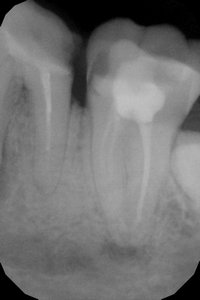

Стояла 8 лет пломба, она выпала, под ней почти ничего, осталось буквально две стенки и те почерневшие. Стою перед выбором: пытаться ли его лечить или удалять?

Врач сказал, что лечение при такой картине с двумя воспаленными корневыми каналами предстоит долгое и мучительное, с необходимостью разрезать десну. Вероятность того, что будут осложнения и в итоге зуб придется удалять, велика.

На верхушках корней, возможно, имеются изменения и открытая бифуркация.